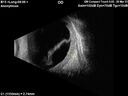

58 year old female The patient noticed decreased vision in the right eye about 2.5 months ago. (you may want to omit this initially -> ) 3 months ago she found a lump in her breast and had stage IV cancer which had spread. It is in her bone, lung. She is starting radiation tomorrow on a couple of vertebrate. Medical Hx: (Onset: 3/28/2023). Breast Cancer Stage 4. Hypertension, Systemic. Surgical Hx: Tonsillectomy. C-Section. Systemic Meds: Propranolol Hydrochloride, 80 mg oral tablet qday. PROCHLORPERAZINE 10MG qday. ANASTROZOLE 1 mg ORAL TABLET, FILM COATED [Anastrozole] qday. Dexamethasone 400 MCG/0.1ML PFS qday. VA OD: Dcc20/200 VA OS: Dcc20/63 IOP: TP: OD:12 OS:15 Put breast cancer history here: Had 10 sessions of radiation to the right eye starting 4/2023 and ending 04/26/23. Also - 4/2023 - kisqali and letrosole (forever drugs) 12/12/23 - Retinal detachment almost completely resolved – Exudative RD took 8 months to resolve. – VA improved from 20/200 to 20/40 (last visit)

Choroidal Metastatic Breast Cancer with Exudative Detachment109 views58 year old female presented with 20/200 vision. Had 10 sessions of radiation and tumor shrank. The exudative detachment took almost a year to resolve. The vision improved to 20/40.00000